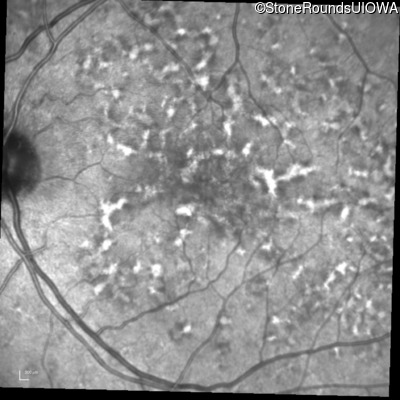

Age at visit: 49 years

OD OS

This 49 year old man was first told he had a fundus abnormality on a routine eye exam at age 34. Ten years later he noticed some distortion just superior to fixation.

Age at visit: 49 years (Visit 2)

Pattern Dystrophy PRPH2 Gln239Stop CAG>TAG   AD